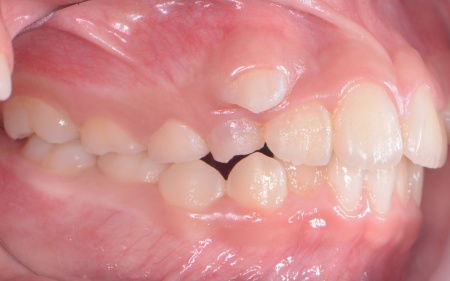

| カウンセリング | 拝見したところ、上の犬歯が歯列の外側に飛び出すように生えている、いわゆる八重歯でした。 さらに、上下の歯全体がデコボコに生えている「叢生(そうせい)」と呼ばれる状態で、これは歯が正しい位置に並ぶためのスペースが不足していることが原因だと考えられます。 このまま放置して顎の成長が完了してから矯正治療を行う場合、歯を並べるスペースを確保することが難しく、永久歯を抜く処置が必要になるケースがあります。 以上のことから、今の段階で歯並びを整える治療が必要だと診断しました。 |

患者様のご家族は「将来的な抜歯はできるだけ避けたいので、今のうちに治療をしたい」と希望されたため、成長期の段階で歯列を広げ、歯が並ぶスペースを確保する小児期の矯正治療「1期矯正」を提案しました。

メリット デメリット また、治療にあたりお口全体のバランスを確認したところ口元の突出はなく、顎のサイズはやや小さめですが、成長期であることから歯列の拡大が可能な状態だと判断しています。 以上の内容について丁寧に説明し、治療に同意いただきました。 まず、上顎に顎の骨を広げるための固定式の矯正器具「急速拡大装置」を、下顎には歯並びの幅を広げるための「リンガルアーチ」を装着します。 次に歯の位置を整えるため、ワイヤー矯正を開始します。 最後に、歯並びが整って見た目や噛み合わせにも問題がないことを確認し、装置を取り外して第1期矯正治療を終了しました。 現在も経過観察を継続していますが、歯が元の位置に戻る後戻りも見られず、残っている乳歯から永久歯への生え変わりも順調に進んでいます。 |